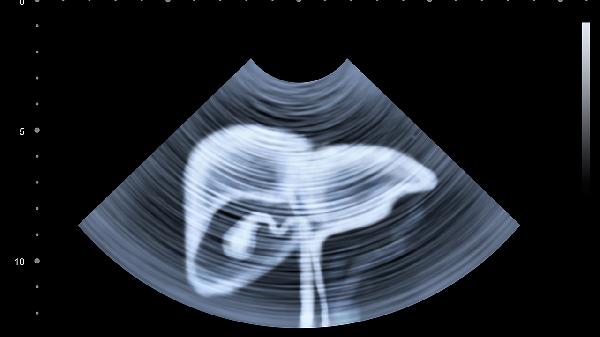

日常可尝试腹式呼吸训练替代机械按压,吸气时腹部隆起维持3秒,呼气时缓慢收缩,重复10次为一组。保持规律饮食和适度运动对胃肠功能调节更安全有效。如出现按压后腹痛加剧、呕血或黑便等情况,应立即停止并就医检查。建议每年进行腹部超声筛查,排除潜在器质性疾病后再考虑腹部按摩干预。